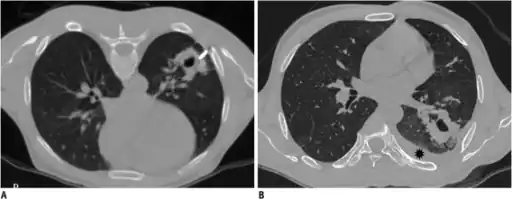

Computed tomography (CT or CAT) scans may be useful for diagnosing retained hemothorax as this form of imaging can detect much smaller amounts of fluid than a plain chest X-ray. However, CT is less used as a primary means of diagnosis within the trauma setting, as these scans require a critically ill person to be transported to a scanner, are slower, and require the subject to remain supine.[23][26]

- CT scan of the chest showing a hemothorax caused by warfarin use